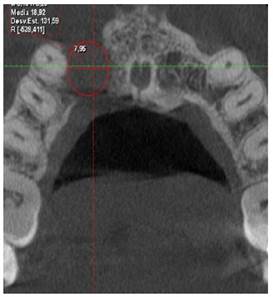

Se realiza el segundo control tomográfico en fecha 11 de noviembre de 2023 donde el tamaño del quiste en sentido longitudinal es de 10,35 mm y en sentido transversal de 7,95 mm (Figura 5a y 5b), observando una reducción considerable del quiste se decide realizar la segunda intervención quirúrgica, donde se hizo la enucleación del quiste y extracción de la pieza 1.2, esta presentaba dos perforaciones laterales y fue valorada previamente por endodoncia, que indico la extracción de la pieza y realizaron las endodoncias de las piezas 1,1 y 1,3 por la cercanía a la lesión quística.

Figura 5a Tomografía 11/11/2023, se observa neoformación ósea alrededor de la lesión y una disminución en la altura a 10,35 mm.

Figura 5b Tomografía corte axial 11/11/2023, se observa neoformación ósea alrededor de la lesión y disminución del ancho de la misma a 7,95 mm.